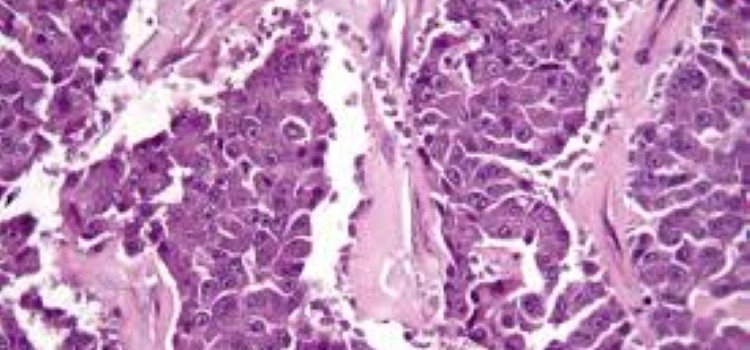

Una combinación de inmunoterapia y quimioterapia muestra eficacia contra el cáncer de páncreas por primera vez

27.05.2020

Hospitales españoles participan en un estudio multicéntrico que registra resultados prometedores contra el cáncer de páncreas, para el que hay pocos tratamientos y cuya incidencia crece